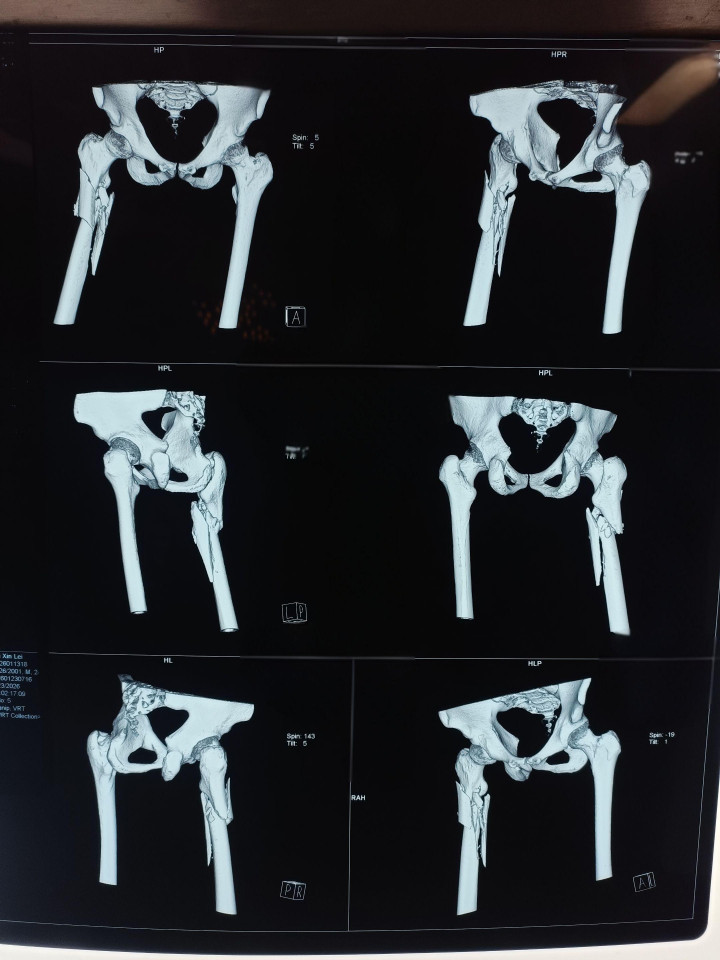

中股网 外伤导致的股骨上段骨折闭合复位股骨重建钉固定,期待早期愈合